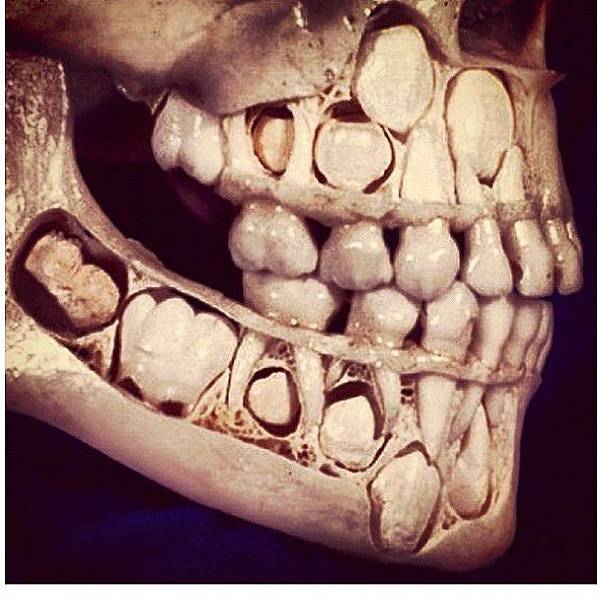

人的一生有兩副牙齒。一般來講,在六周歲開始,乳牙逐漸鬆動脫落,替換出相應的恒牙。替牙期是否良好護理,直接關係到今後恒牙的使用效率和壽命。在替牙期,家長和孩子們經常會有些疑問

(1)到底換多少顆牙?